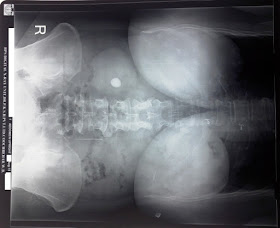

Her abdominal X-ray also reveals a right renal stone although she never complained of renal colic.

PATIENT'S HISTORY: The patient is a 60-year-old housewife. In 2013, she had an episode of probable stroke followed by nausea, vomiting, diarrhea, weakness, fatigue with loss of appetite, and insomnia. Her legs felt numb. She lost sensation around neck. Had to be admitted to a nursing home. Diagnosis of hypocalcemia and hypokalemia was made. Got discharged after 5 days when k+ and Ca2+ lvl. returned to normal via i.v infusion. For 2 yrs she was fine. In 2015, due to diarrhea and fatigue she got admitted to a Nursing home and stayed there for 7 days. Ca2+ and K+ lvl. was falling, so restored via i.v infusion. This time hypernatremia was also detected. Discharged after her conditions improved. But 2 days later, again due to severe diarrhea had to be admitted to a Nursing home for 19 days. During her stay USG of abdomen, colposcopy and chest X-ray was done. USG detected a large renal calculus measuring 22mm in rt. kidney. Sx was recommended. Pt went to Bhopal for a second opinion.

Clinician advised against surgery because she was not in pain. Her TSH is normal. A CT abdomen revealed a left adrenal cortical tumor. Diagnosis of pri. aldosteronism was made. Patient is hypertensive since 1995 since her second childbirth. Now BP is normal with medication. She is nondiabetic. Pt. advised to report her Ca2+ and K+ lvl. monthly. Pt. acq. the habit of eating paan (beetle leaf) from her mother in 2011 when she came to stay with her. Used to eat 3-4 paans a day. Stopped in 2013 after Dr. advised against it.